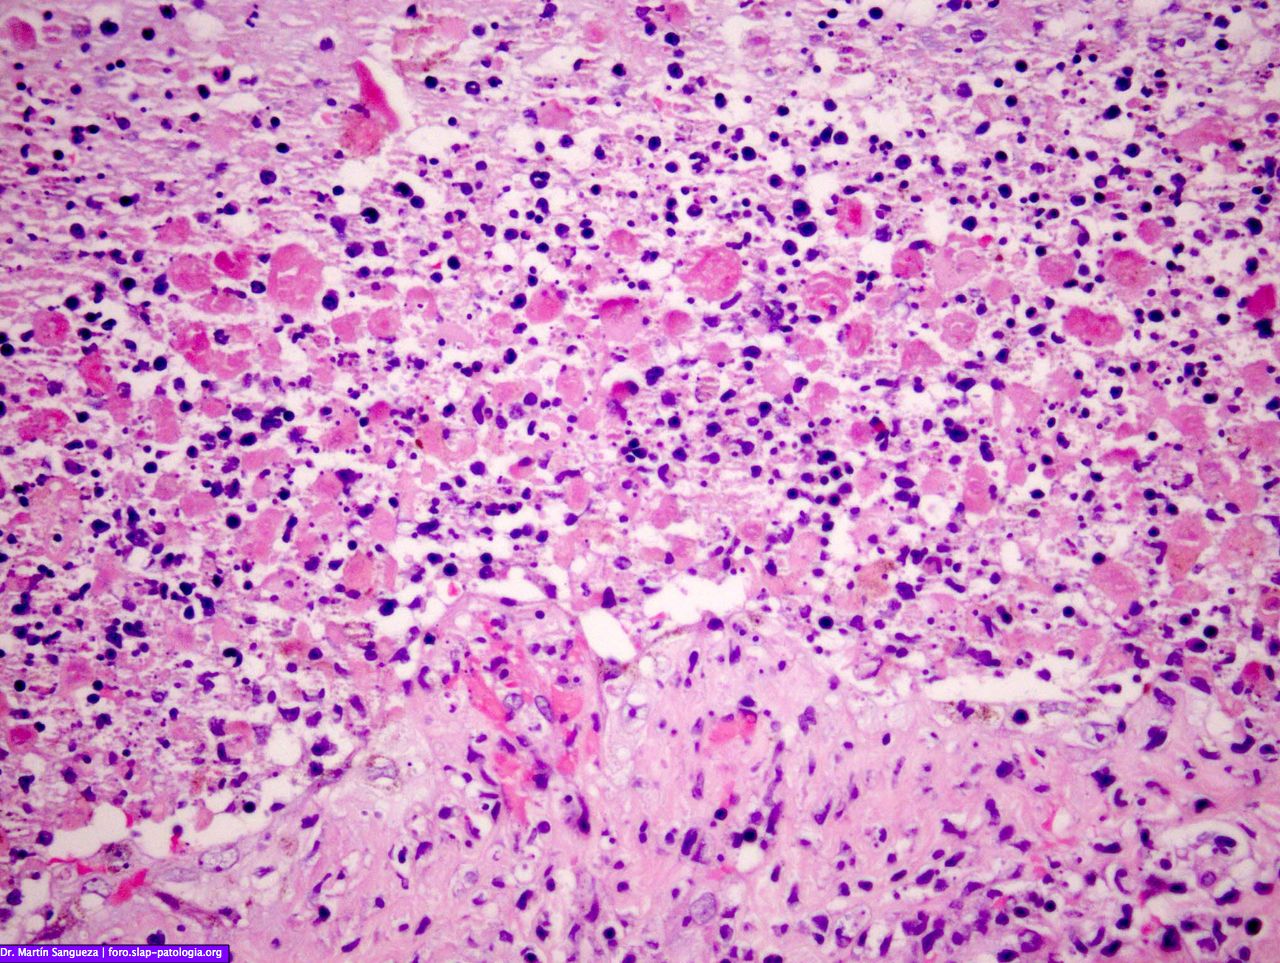

Межуточный миокардит: гистологические исследования